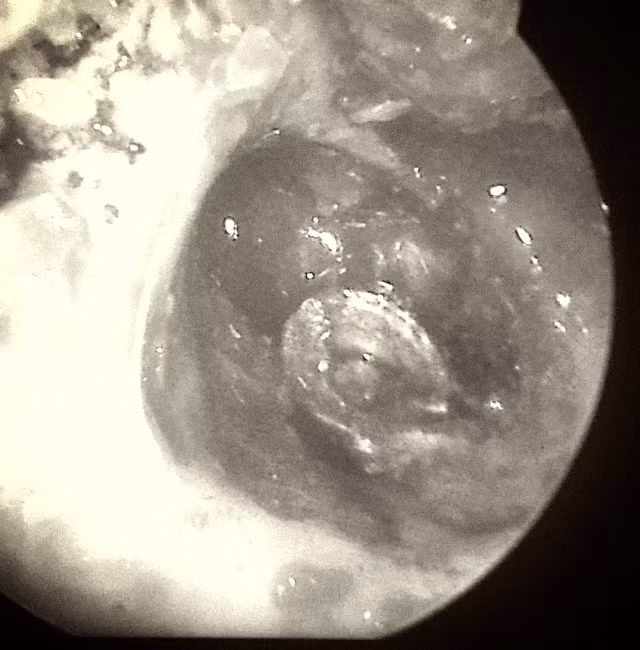

Viên đạn ghém (màu bạc) trước khi được lấy ra khỏi tai. Nguồn: Bệnh viện Trung ương Thái Nguyên.

Ths.Bs Nguyễn Thị Phương Thúy, Khoa Tai - Mũi - Họng, thành viên kíp mổ cho biết thêm: Trong quá trình phẫu thuật, toàn bộ vùng xương chũm của tai đã bị viêm nhiễm hoàn toàn, kíp mổ phải áp dụng kỹ thuật mở sào bào ( kỹ thuật dùng khoan mở rộng thành ống tai để quan sát hòm nhĩ rõ ràng nhất), lấy hết các tổ chức viêm, gắp đạn và những mảnh vụn ra khỏi tai bệnh nhân.